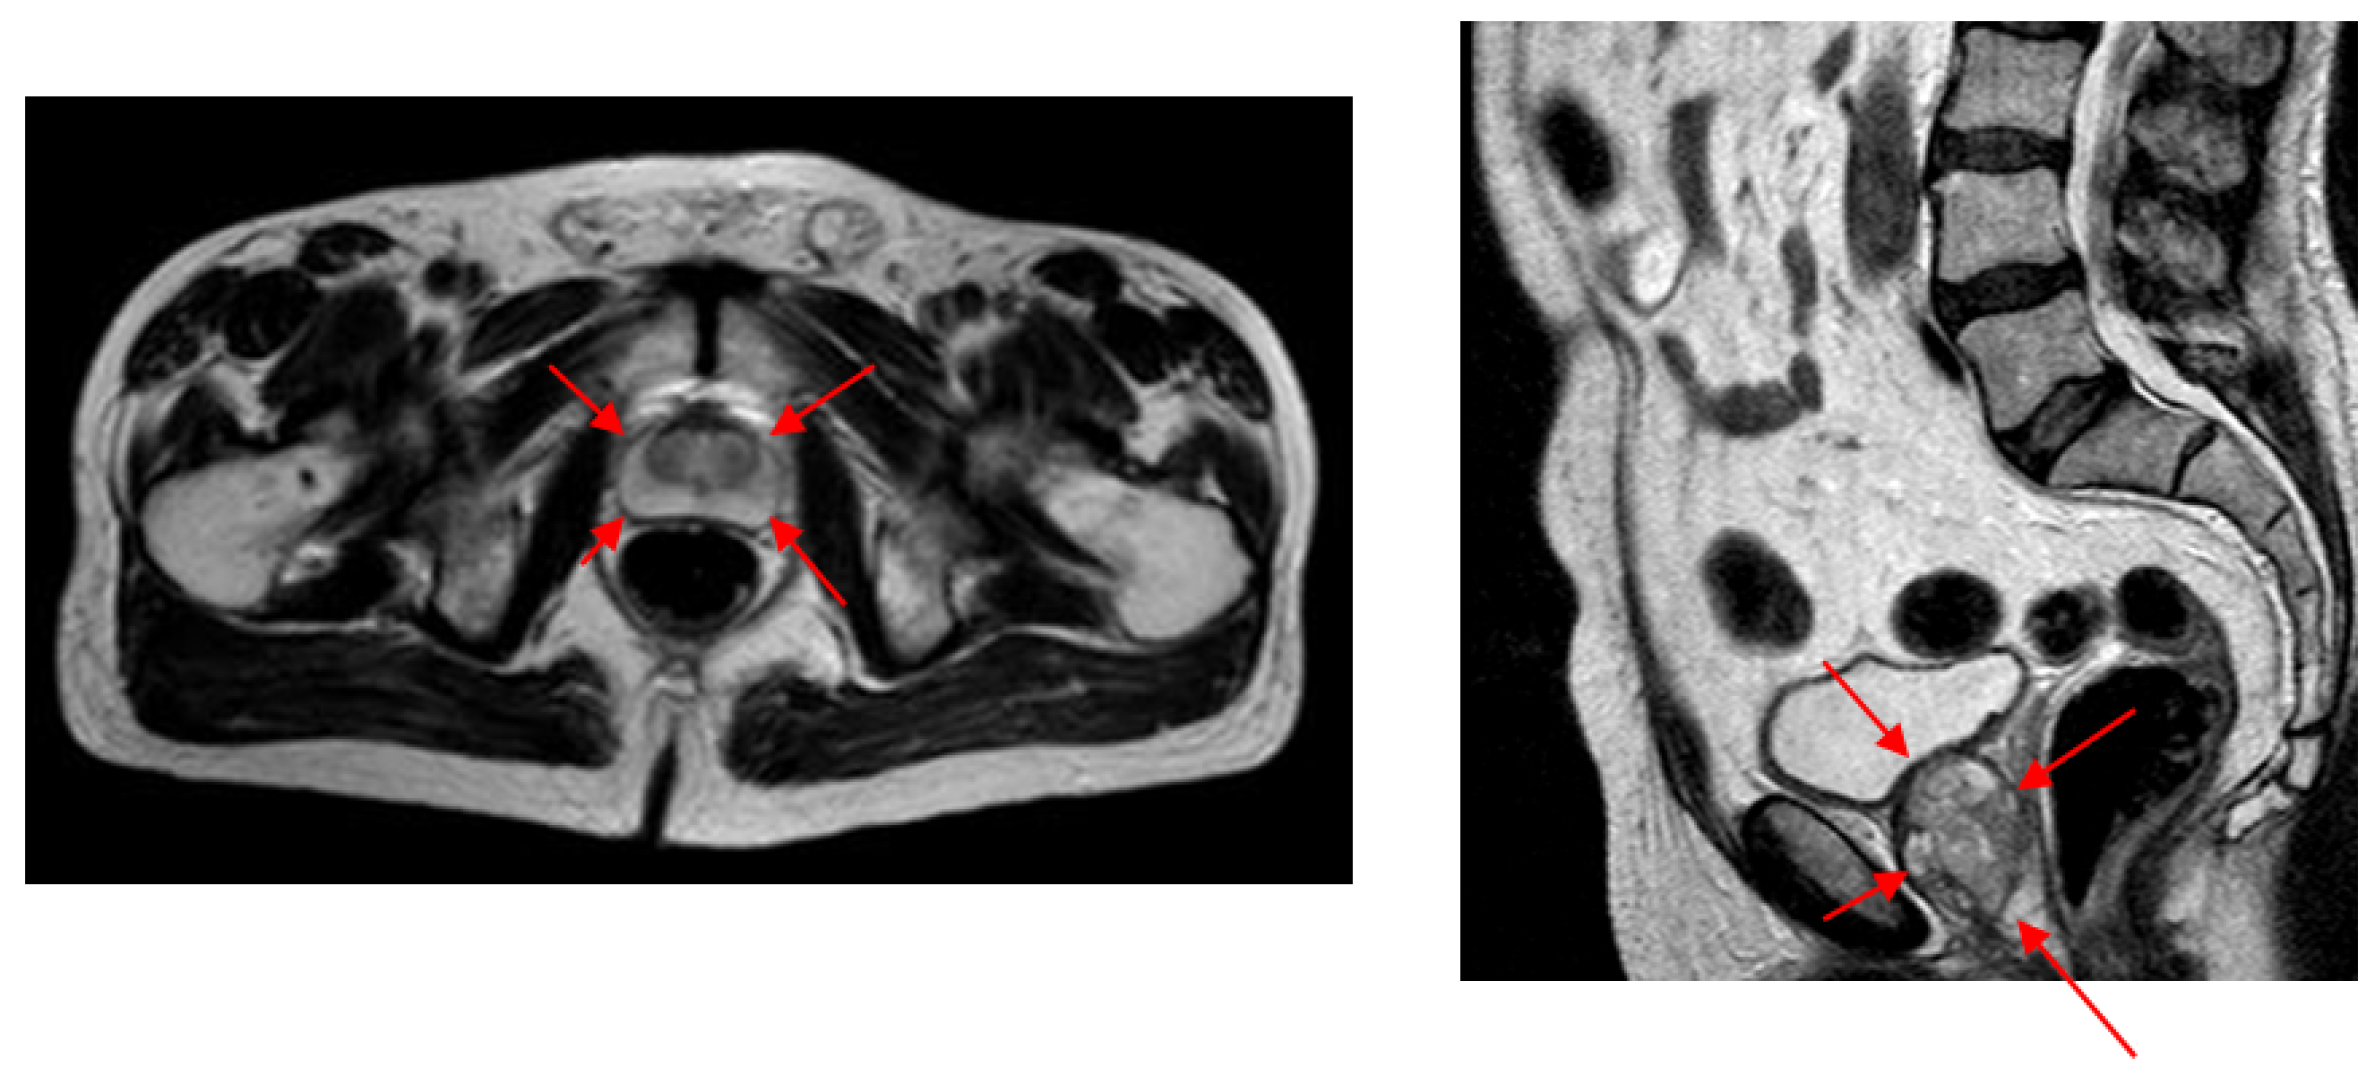

There are many medical-imaging technologies to estimate prostate volume. Widely used technologies are Magnetic Resonance Imaging (MRI), Computed Tomography (CT), and Ultrasound (US) [8]. US technology differs from others with its portability, low-cost, and harmlessness, and it allows experts to scan the prostate in real-time [9]. Trans Rectal Ultrasound (TRUS) and Abdominal Ultrasound (AUS) technologies are frequently used in prostate applications. As shown in Figure 1, despite its better imaging quality with a higher Signal-to-Noise Ratio (SNR) and a larger view of the prostate with no other anatomic structures, TRUS technology is difficult to use regularly during successive radiotherapy sequences [10] due to patient discomfort [11]. The AUS technique is an easy-to-use alternative US imaging technology and is often used where TRUS is not practical.

We were unable to compare our volume-estimation results with other studies as almost no other studies are available to estimate prostate volume from AUS images. Instead, we evaluated the difference in intra- and inter-expert volume estimates on AUS images and compared these values with our system estimates. Due to the higher SNR values and better image quality compared (Figure 2) to both AUS and TRUS images (Figure 1), MR image annotations are considered the gold standard [13] in prostate applications. Accordingly, we also evaluated the intra- and inter-expert volume estimation difference in MR images and compared these values with our system’s volume estimations and expert estimations on AUS images. The results show that our system achieved the volume estimate difference values of human experts.

Figure 1. Comparison of AUS and TRUS images of the prostate from transverse plane. While AUS images have lower SNR and contain other anatomical structures, TRUS images have higher SNR, and the prostate is the only anatomical structure contained.